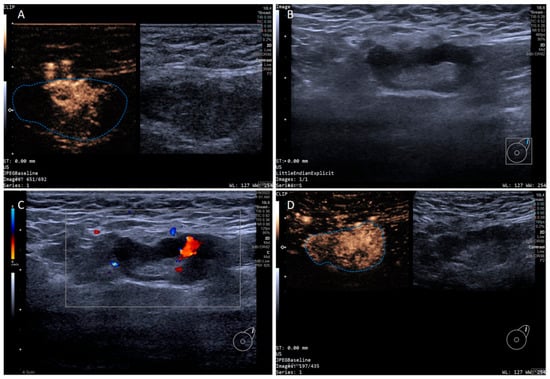

In addition, the SLN-IVCEUS enhancement patterns were divided into four types: type I showed homogeneous high enhancement; type II showed diffuse inhomogeneous high enhancement; type III showed no/low enhancement of the lymphatic hilus, homogeneous high enhancement of the cortex; type IV showed part of the cortical filling defect, low enhancement or high enhancement, the rest showed the performance of types I, II or III. And SLN-IVCEUS enhancement sequence was divided into three types based on the orders of bubbles entering the lymph nodes: centrifugal enhancement, centripetal enhancement, and diffuse enhancement. A malignant lymph node was diagnosed as long as one of the following conditions was met: (I) centripetal enhancement; (II) diffuse enhancement; (III) the enhancement mode of IVCEUS was type IV. SLN was diagnosed as malignant when PCEUS and/or IVCEUS diagnosed the SLN as malignant (Figure 2 and Figure 3).

Figure 2. Multimodal ultrasound imaging of pathologically confirmed non-metastatic sentinel lymph node. (A) Intradermal CEUS image (the enhancement pattern is type VIc, the blue dotted line delineates the contour of the SLN); (B) 2D US image; (C) Color Doppler Flow Imaging (CDFI) image; (D) intravenous CEUS image (the enhancement pattern is III, the blue dotted line delineates the contour of the SLN).